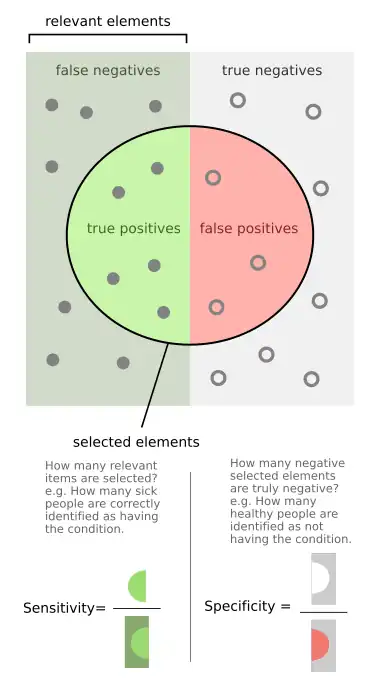

In medicine and statistics, sensitivity and specificity mathematically describe the accuracy of a test that reports the presence or absence of a medical condition. If individuals who have the condition are considered "positive" and those who do not are considered "negative", then sensitivity is a measure of how well a test can identify true positives and specificity is a measure of how well a test can identify true negatives:

- Sensitivity (true positive rate) is the probability of a positive test result, conditioned on the individual truly being positive.

- Specificity (true negative rate) is the probability of a negative test result, conditioned on the individual truly being negative.

Imagine a study evaluating a test that screens people for a disease. Each person taking the test either has or does not have the disease. The test outcome can be positive (classifying the person as having the disease) or negative (classifying the person as not having the disease). The test results for each subject may or may not match the subject's actual status. In that setting:

- True positive: Sick people correctly identified as sick

- False positive: Healthy people incorrectly identified as sick

- True negative: Healthy people correctly identified as healthy

- False negative: Sick people incorrectly identified as healthy

After getting the numbers of true positives, false positives, true negatives, and false negatives, the sensitivity and specificity for the test can be calculated. If it turns out that the sensitivity is high then any person who has the disease is likely to be classified as positive by the test. On the other hand, if the specificity is high, any person who does not have the disease is likely to be classified as negative by the test. An NIH web site has a discussion of how these ratios are calculated.[3]

Sensitivity

Consider the example of a medical test for diagnosing a condition. Sensitivity (sometimes also named the detection rate in a clinical setting) refers to the test's ability to correctly detect ill patients out of those who do have the condition.[4] Mathematically, this can be expressed as:

Specificity

Consider the example of a medical test for diagnosing a disease. Specificity refers to the test's ability to correctly reject healthy patients without a condition. Mathematically, this can be written as: